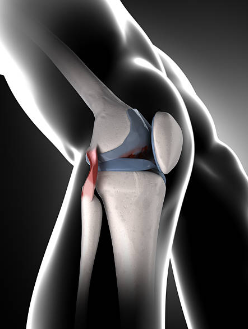

6. 퇴행성 반월상 연골 파열

퇴행성 반월상 연골 파열은 나이가 들면서 반월상 연골이 약해지고 손상되는 질환입니다. 퇴행성 반월상 연골 파열이 발생하면 무릎 안쪽 통증이 발생하며, 부기, 무릎의 잠김 현상, 관절의 움직임 제한 등의 증상이 동반될 수 있습니다. 퇴행성 반

월상 연골 파열은 특별한 외부 요인 없이도 발생할 수 있으며, 나이가 들수록 더 많이 발생합니다.